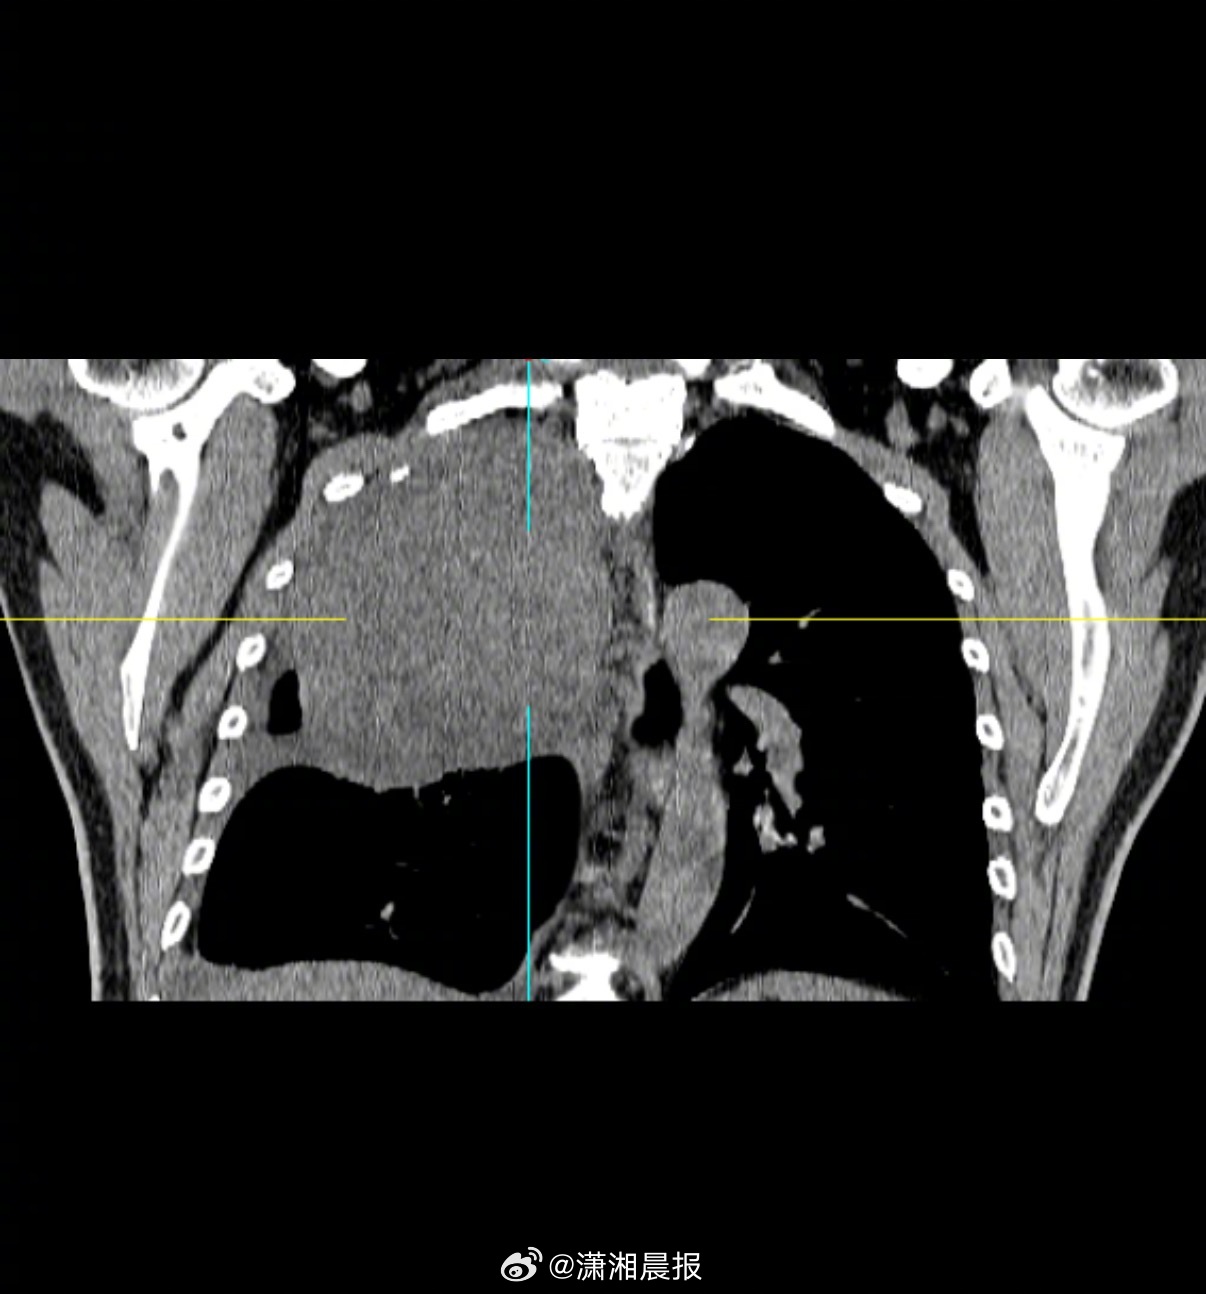

【52岁#男子咳嗽老不好肺部查出16cm肿瘤#】近日,郴州市第一人民医院东院胸部